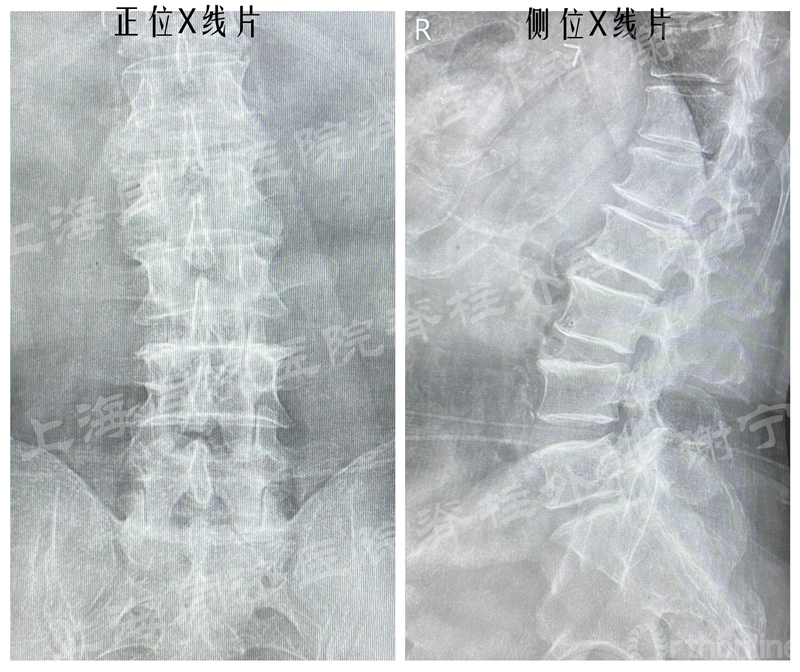

患者男性,66岁,左下肢疼痛麻木2月余,加重3周入院。左直腿抬高征阳性。X线片示腰椎轻度侧弯,未见明显不稳。MR和CT示L5/S1椎间盘脱出,椎间盘合并骨化,中央偏左侧。

图11 术前X线片